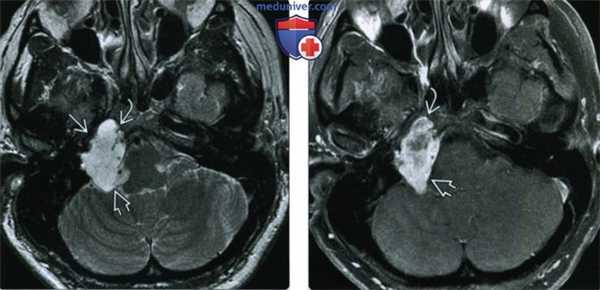

(Слева) При МРТ Т2 в аксиальной проекции определяется гиперинтенсивная хондросаркома верхушки пирамиды правой височной кости, paспpoстpaняющаяся в цистерну правого мостомозжечкового угла. Каменистый сегмент внутренней сонной артерии смещен кпереди.

(Справа) При МРТ Т1 FS с КУ в аксиальной проекции наблюдается интенсивное контрастирование хондросаркомы. Обратите внимание на поражение верхушки пирамиды височной кости и цистерны мостомозжечкового угла. Большинство хондросарком основания черепа возникают в каменисто-затылочной щели. Однако когда опухоль достигает крупных размеров, бывает трудно установить место ее возникновения.